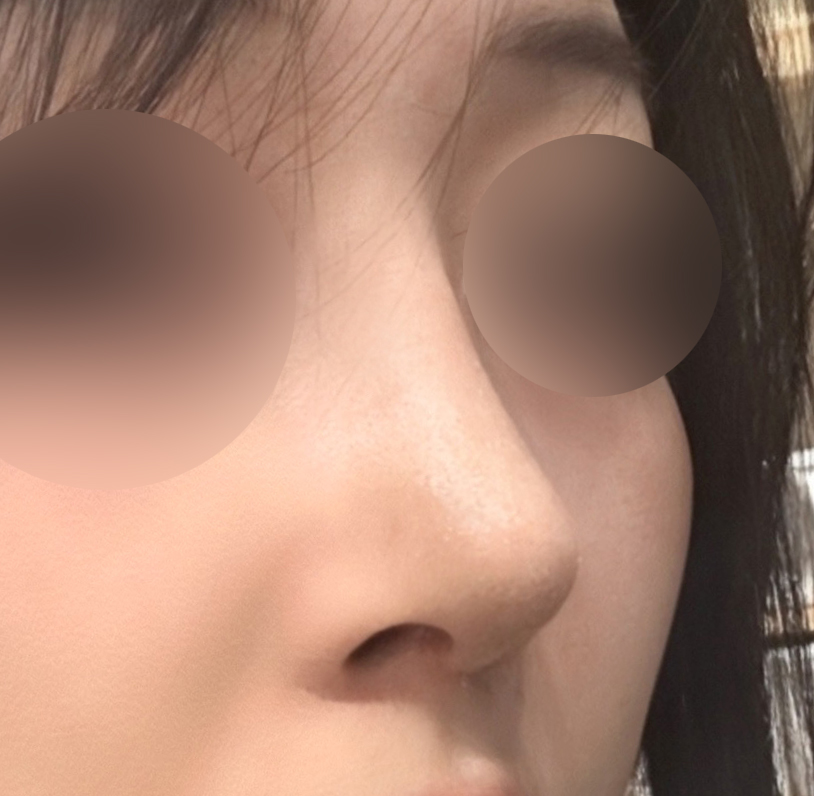

실리콘, 비중격, 귀연골, 기증늑연골사용해서

수술했고 이물질제거와 복코, 용코교정한지

3주차 됐는데요

벌써부터 너무 자연스럽고

평소 고민이었던 용코도 정말 많이 교정되고

자연스럽고 화려한 코라인이 나와서